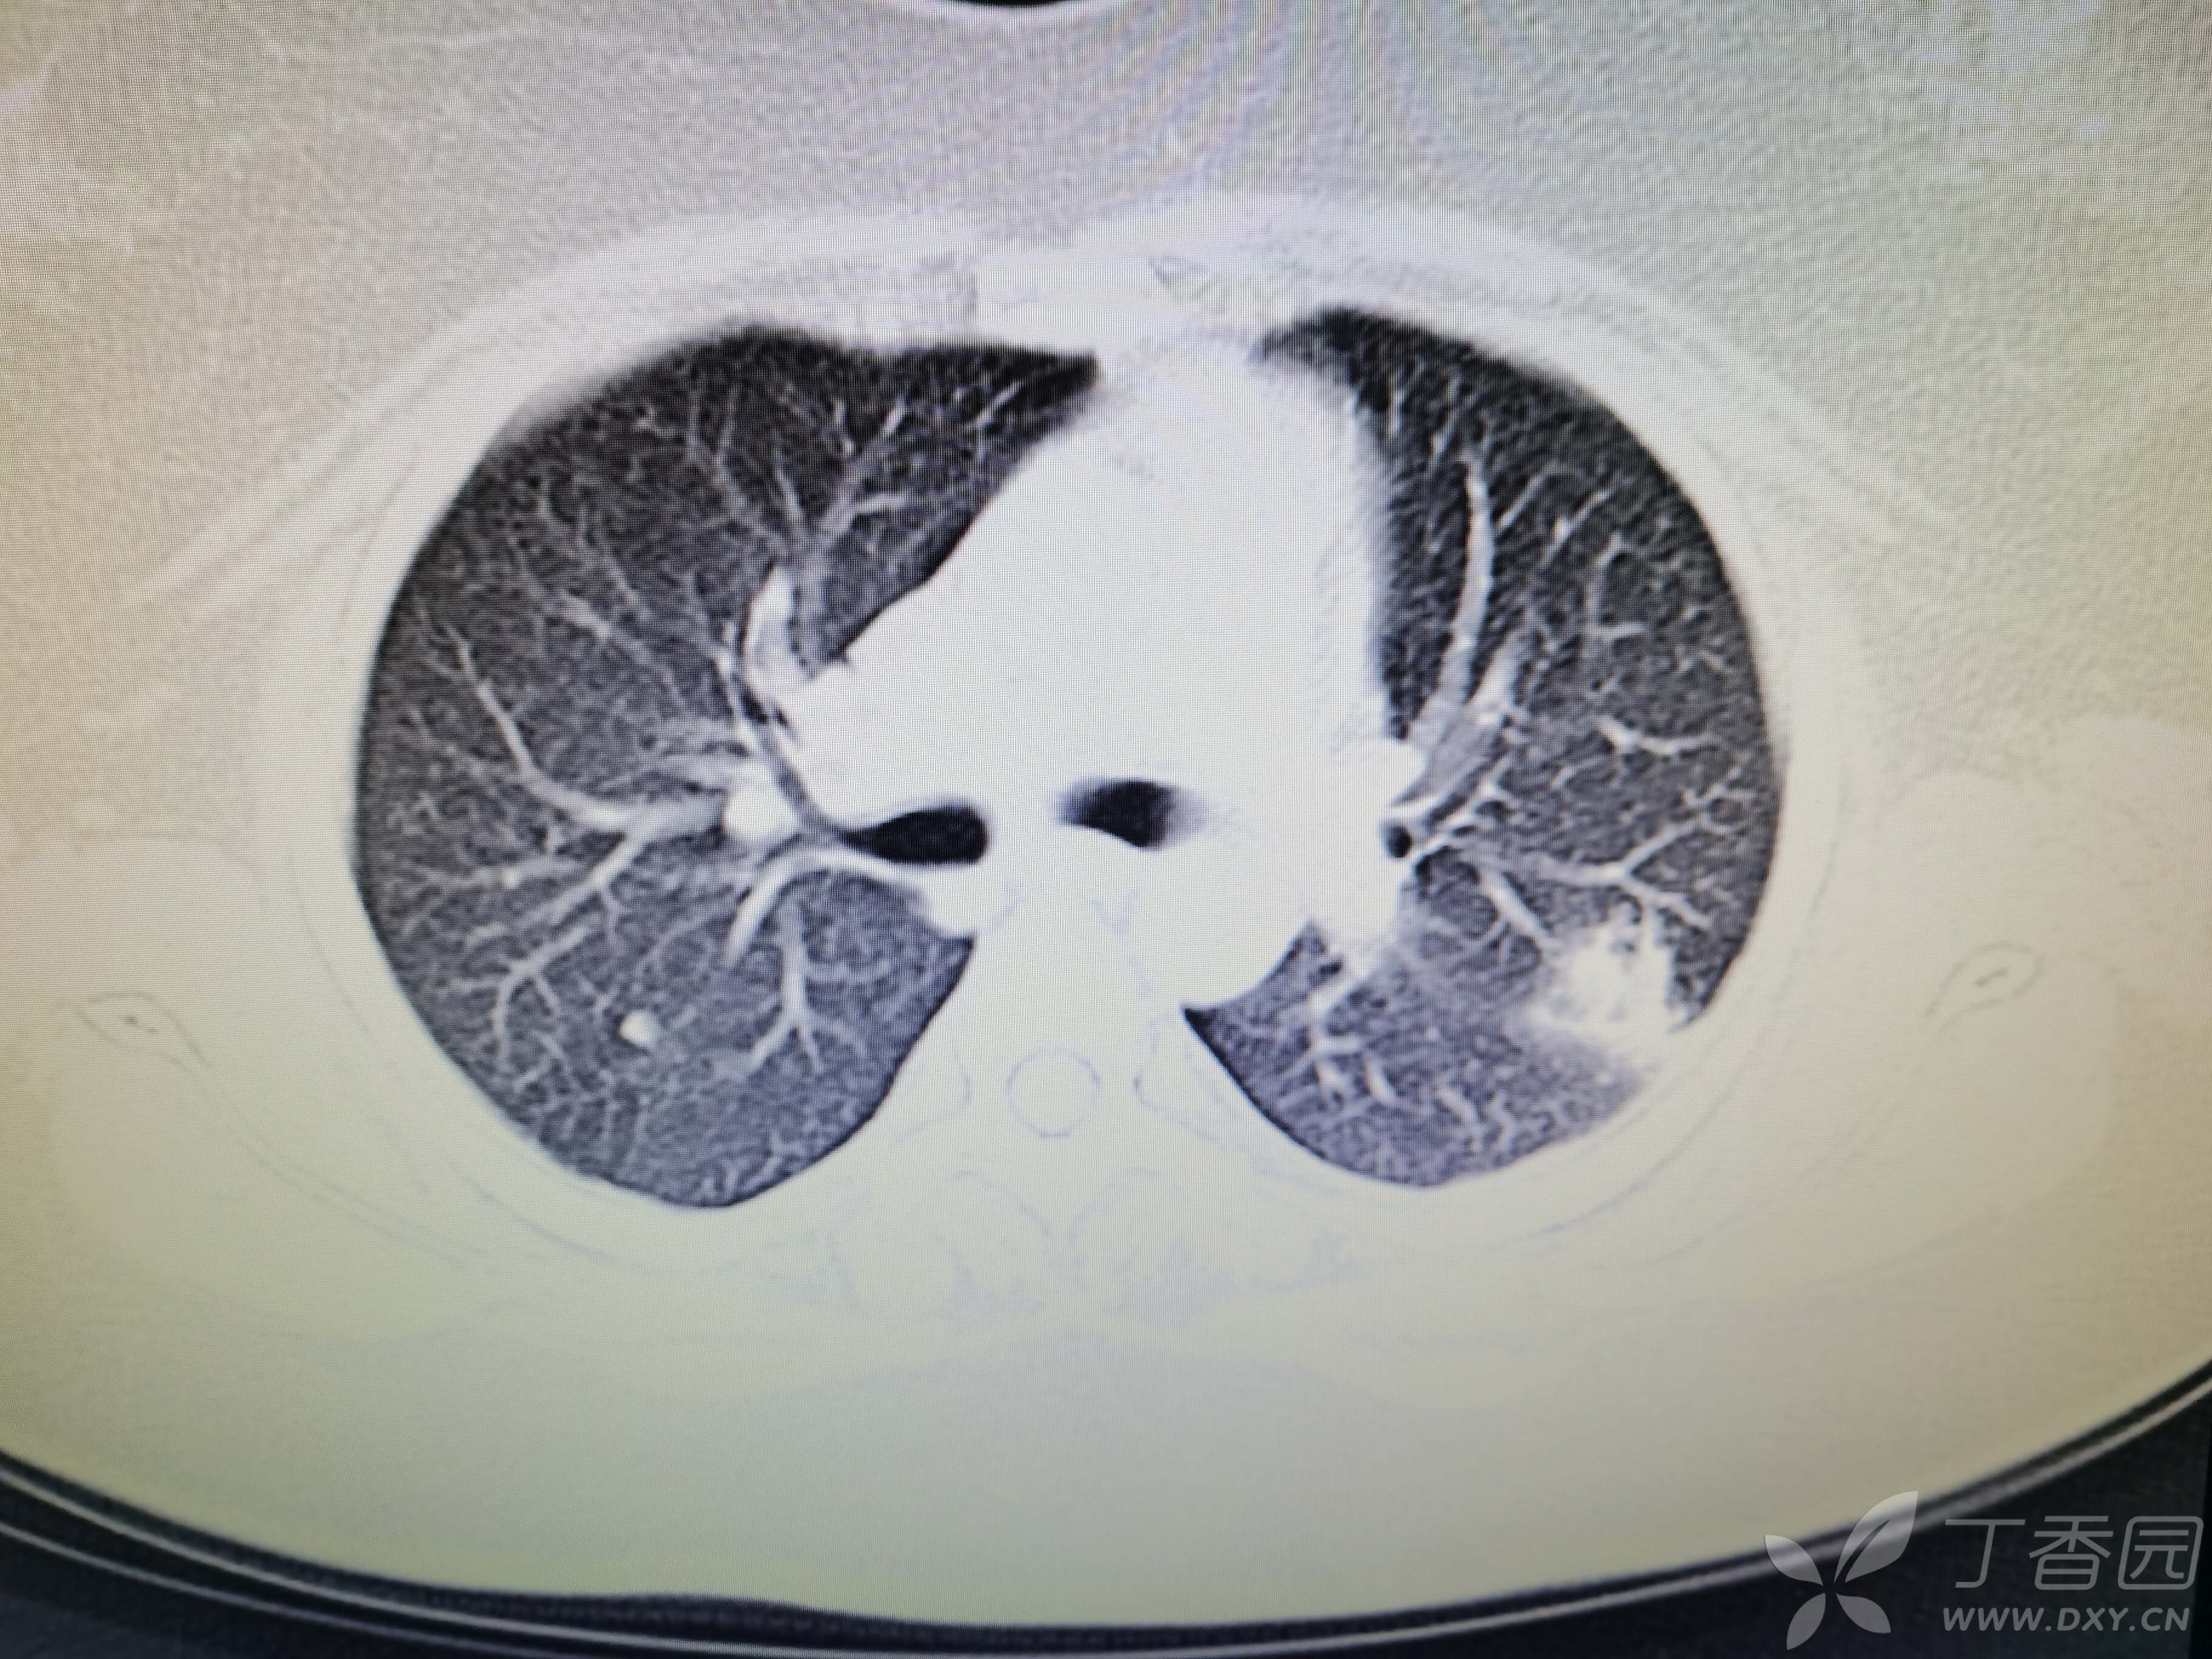

基本信息:女,三十几岁,印度人。。

胸部CT:

如题:猜肺部病灶病理。。